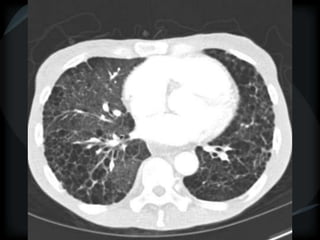

Emphysema - CL

Emphysema - PA

CL + PS emphysema

Hyperlucency

Centrilobular emphysema

Paraseptal emphysema

Panacinar emphysema